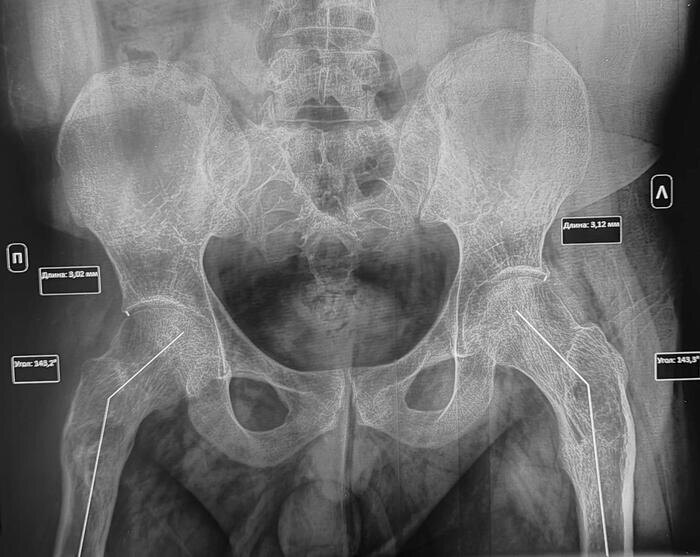

В анамнезе у призывника диагноз- дисплазия тазобедренных суставов, перенесенное оперативное лечение по поводу дисплазии в детстве. По данным рентгенографии костей таза: ШДУ справа 143 град, слева 143 град, сужение суставной щели справа до 3 мм, слева до 3.1 мм, остеофиты по верхне-наружным краям суставных щелей, шейка правой бедренной кости укорочена ,перекос таза вправо. Двусторонние участки разряжения костной ткани в межвертельной области(более выраженно справа)-как следствие перенесенных оперативных вмешательств. Заключение: Coxa valga bilateralis как следствие дисплазии тазобедренных суставов. Вторичный двусторонний коксартроз 1ст.

Перекос таза вправо.

У выше представленного призывника, при измерении истинной длины нижних конечностей, выявлено укорочение правой нижней конечности на 2.5 см., что соответствует ст.69в-В(ограниченно годен к в/сл)